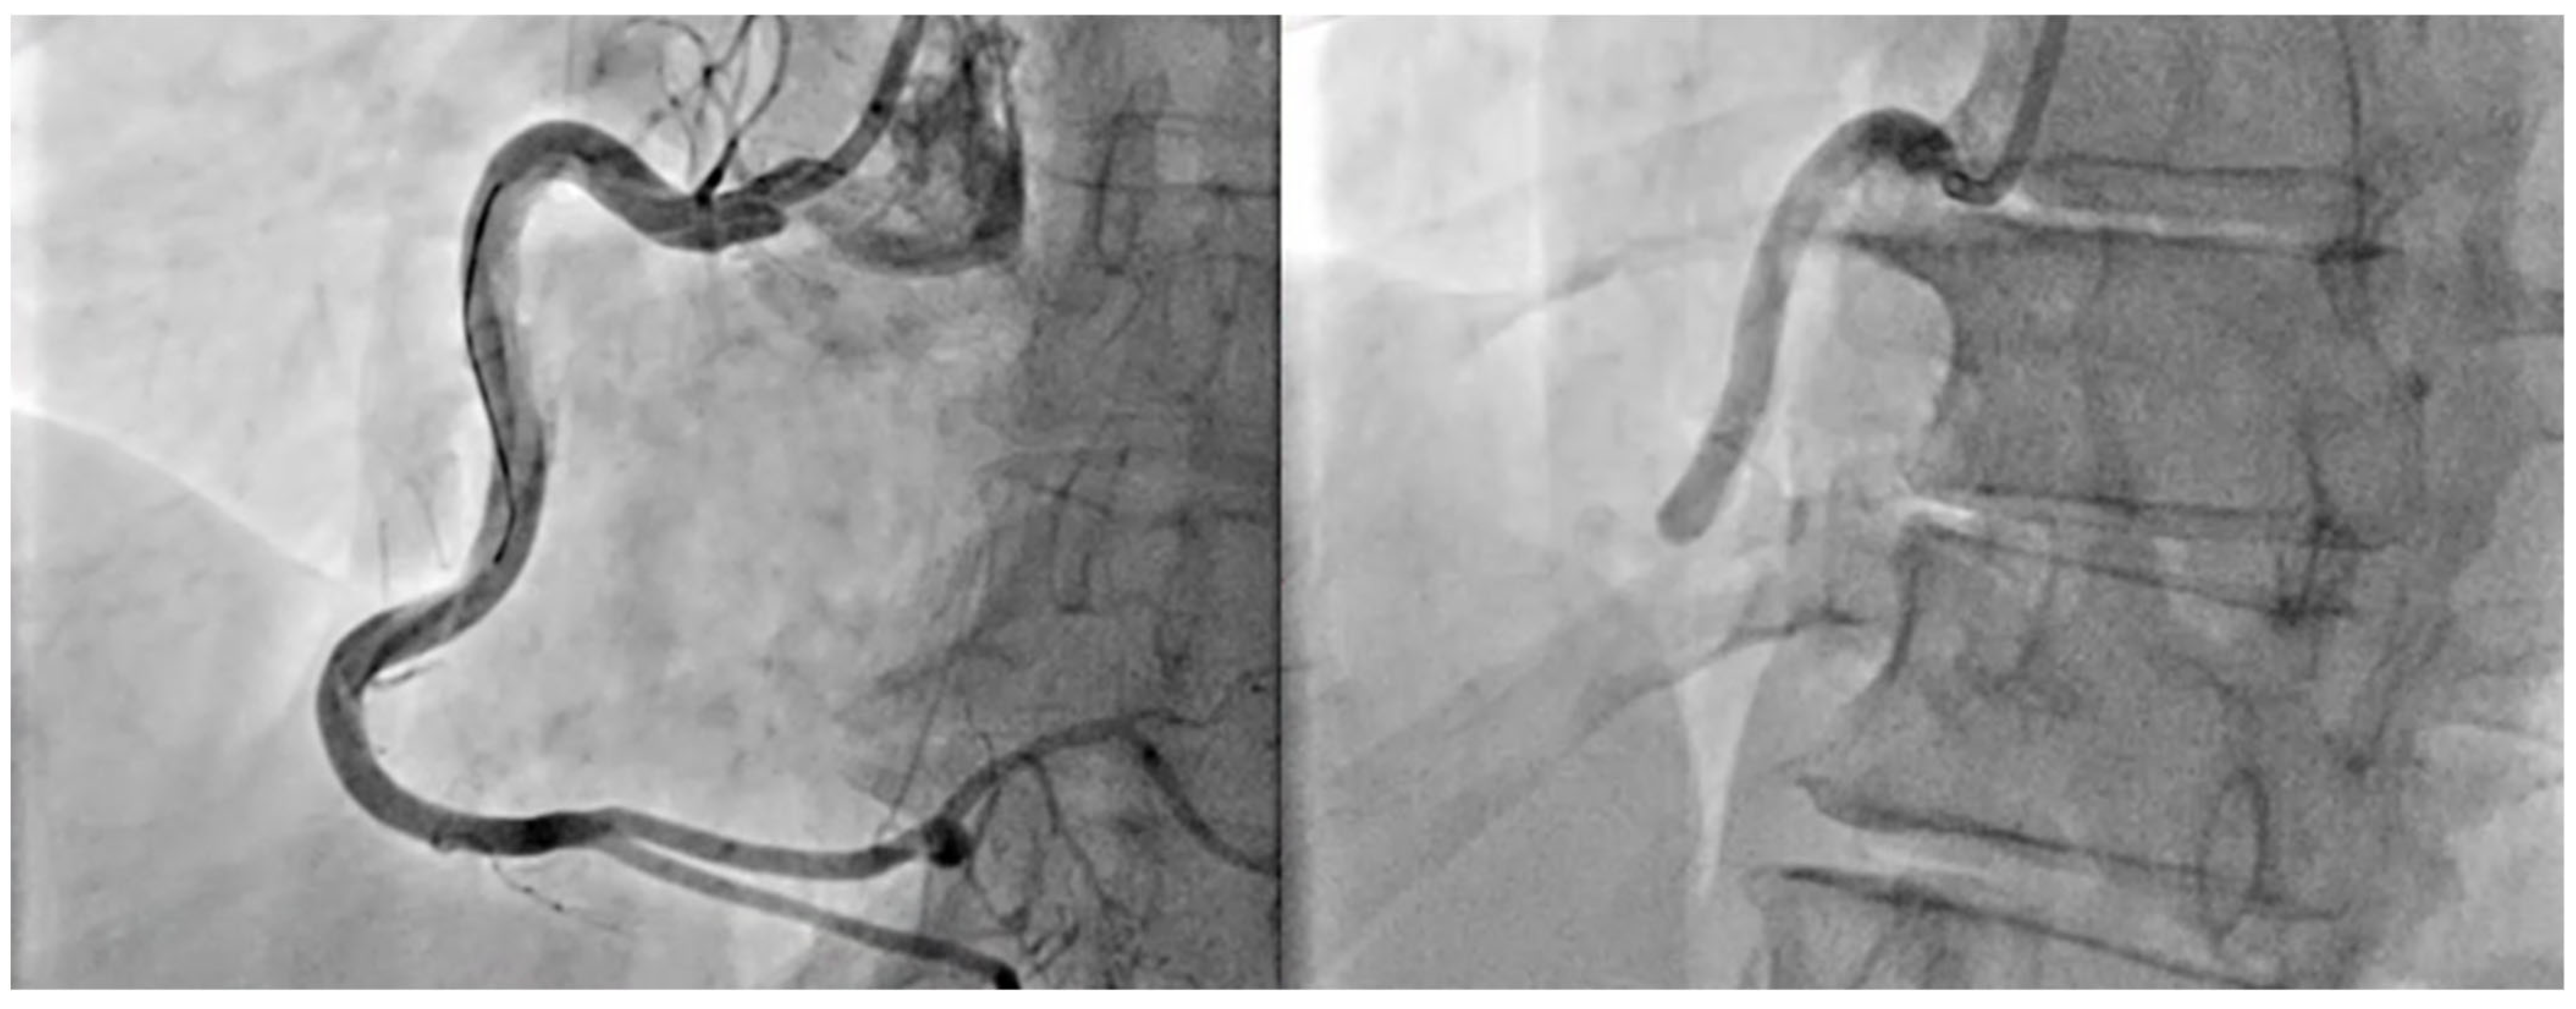

3.1. Diagnostic Approach in Acute Coronary Syndrome

4.1. Treatment of Acute Coronary Syndrome

2.6. Procedural Risks in Stroke Development